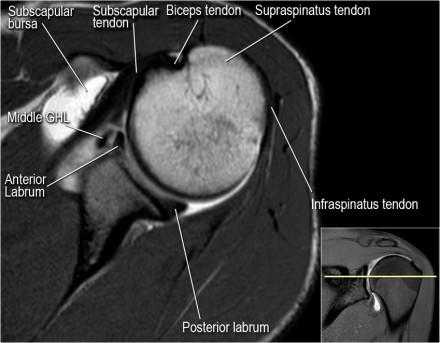

Нормальная анатомия плечевого сустава в аксиальных изображениях и контрольный список.

- волокна сухожилия подлопаточной мышцы, создавая бицепитальную борозду, удерживают сухожилие длинной головки двуглавой мышцы. Изучите хрящи.

- уровень средней плече-лопаточной связки и передних отделов суставной губы. Поищите комплекс Буффорда. Изучите хрящи.

- вогнутость заднебокового края головки плечевой кости не следует путать с повреждением Хилл-Сакса, поскольку это нормальная форма для данного уровня. Повреждение Хилл-Сакса визуализируется только на уровне клювовидного отростка. В предних отделах мы сейчас на урвоне 3-6 часов. Здесь визуализируются повреждение Банкарта и его варианты.